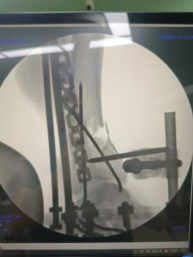

三臂十一軸機器人輔助器牽引,安裝外固定架,透視檢查骨折端對位對線良好。